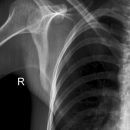

Schulter nach Morrison oder Outlet View

Indikation

v.a. Impingementsyndrom: Beurteilung des Akromions, des AC-Gelenks, evtl. hilfreich zur Diagnostik von Luxationen

Beurteilungskriterien

- Impingementsyndrom (2): Neigungswinkel des Akromions -> Je gebogener bzw. hakenförmiger desto höher ist die Wahrscheinlichkeit. Radiologische Befunde: Zystenbildung im Bereich des Tuberculum majus? Subchondrale Sklerosierung am Tuberculum majus oder subacromiale Osteophytenbildung? Verkalkungen im Verlauf der Supraspinatussehne?

- subacrominalen Raumes: normalerweise 1 - 1,5 cm, < 10 mm -> wahrscheinlich, < 6 mm -> sicher pathologisch